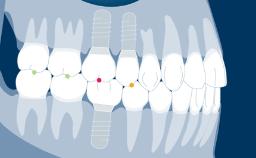

The clinician practicing implant dentistry is confronted with different clinical situations, ranging from a single missing tooth, to an edentulous space with several missing teeth, to complete edentulous ridges.

Once a thorough treatment plan is established, different design configurations may be possible for implant-supported prostheses. Each prosthesis design has its advantages and disadvantages.

- single-tooth spaces

- short edentulous spaces

- extended edentulous spaces

- edentulous ridges